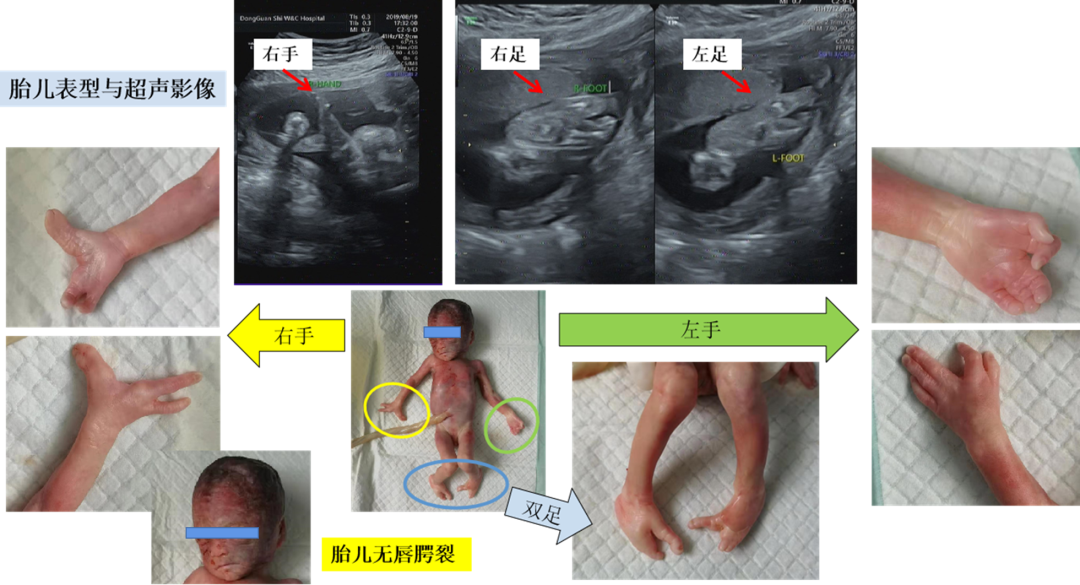

胎儿唇腭裂伴面横裂畸形产前超声表现一例

图片尺寸2008x650